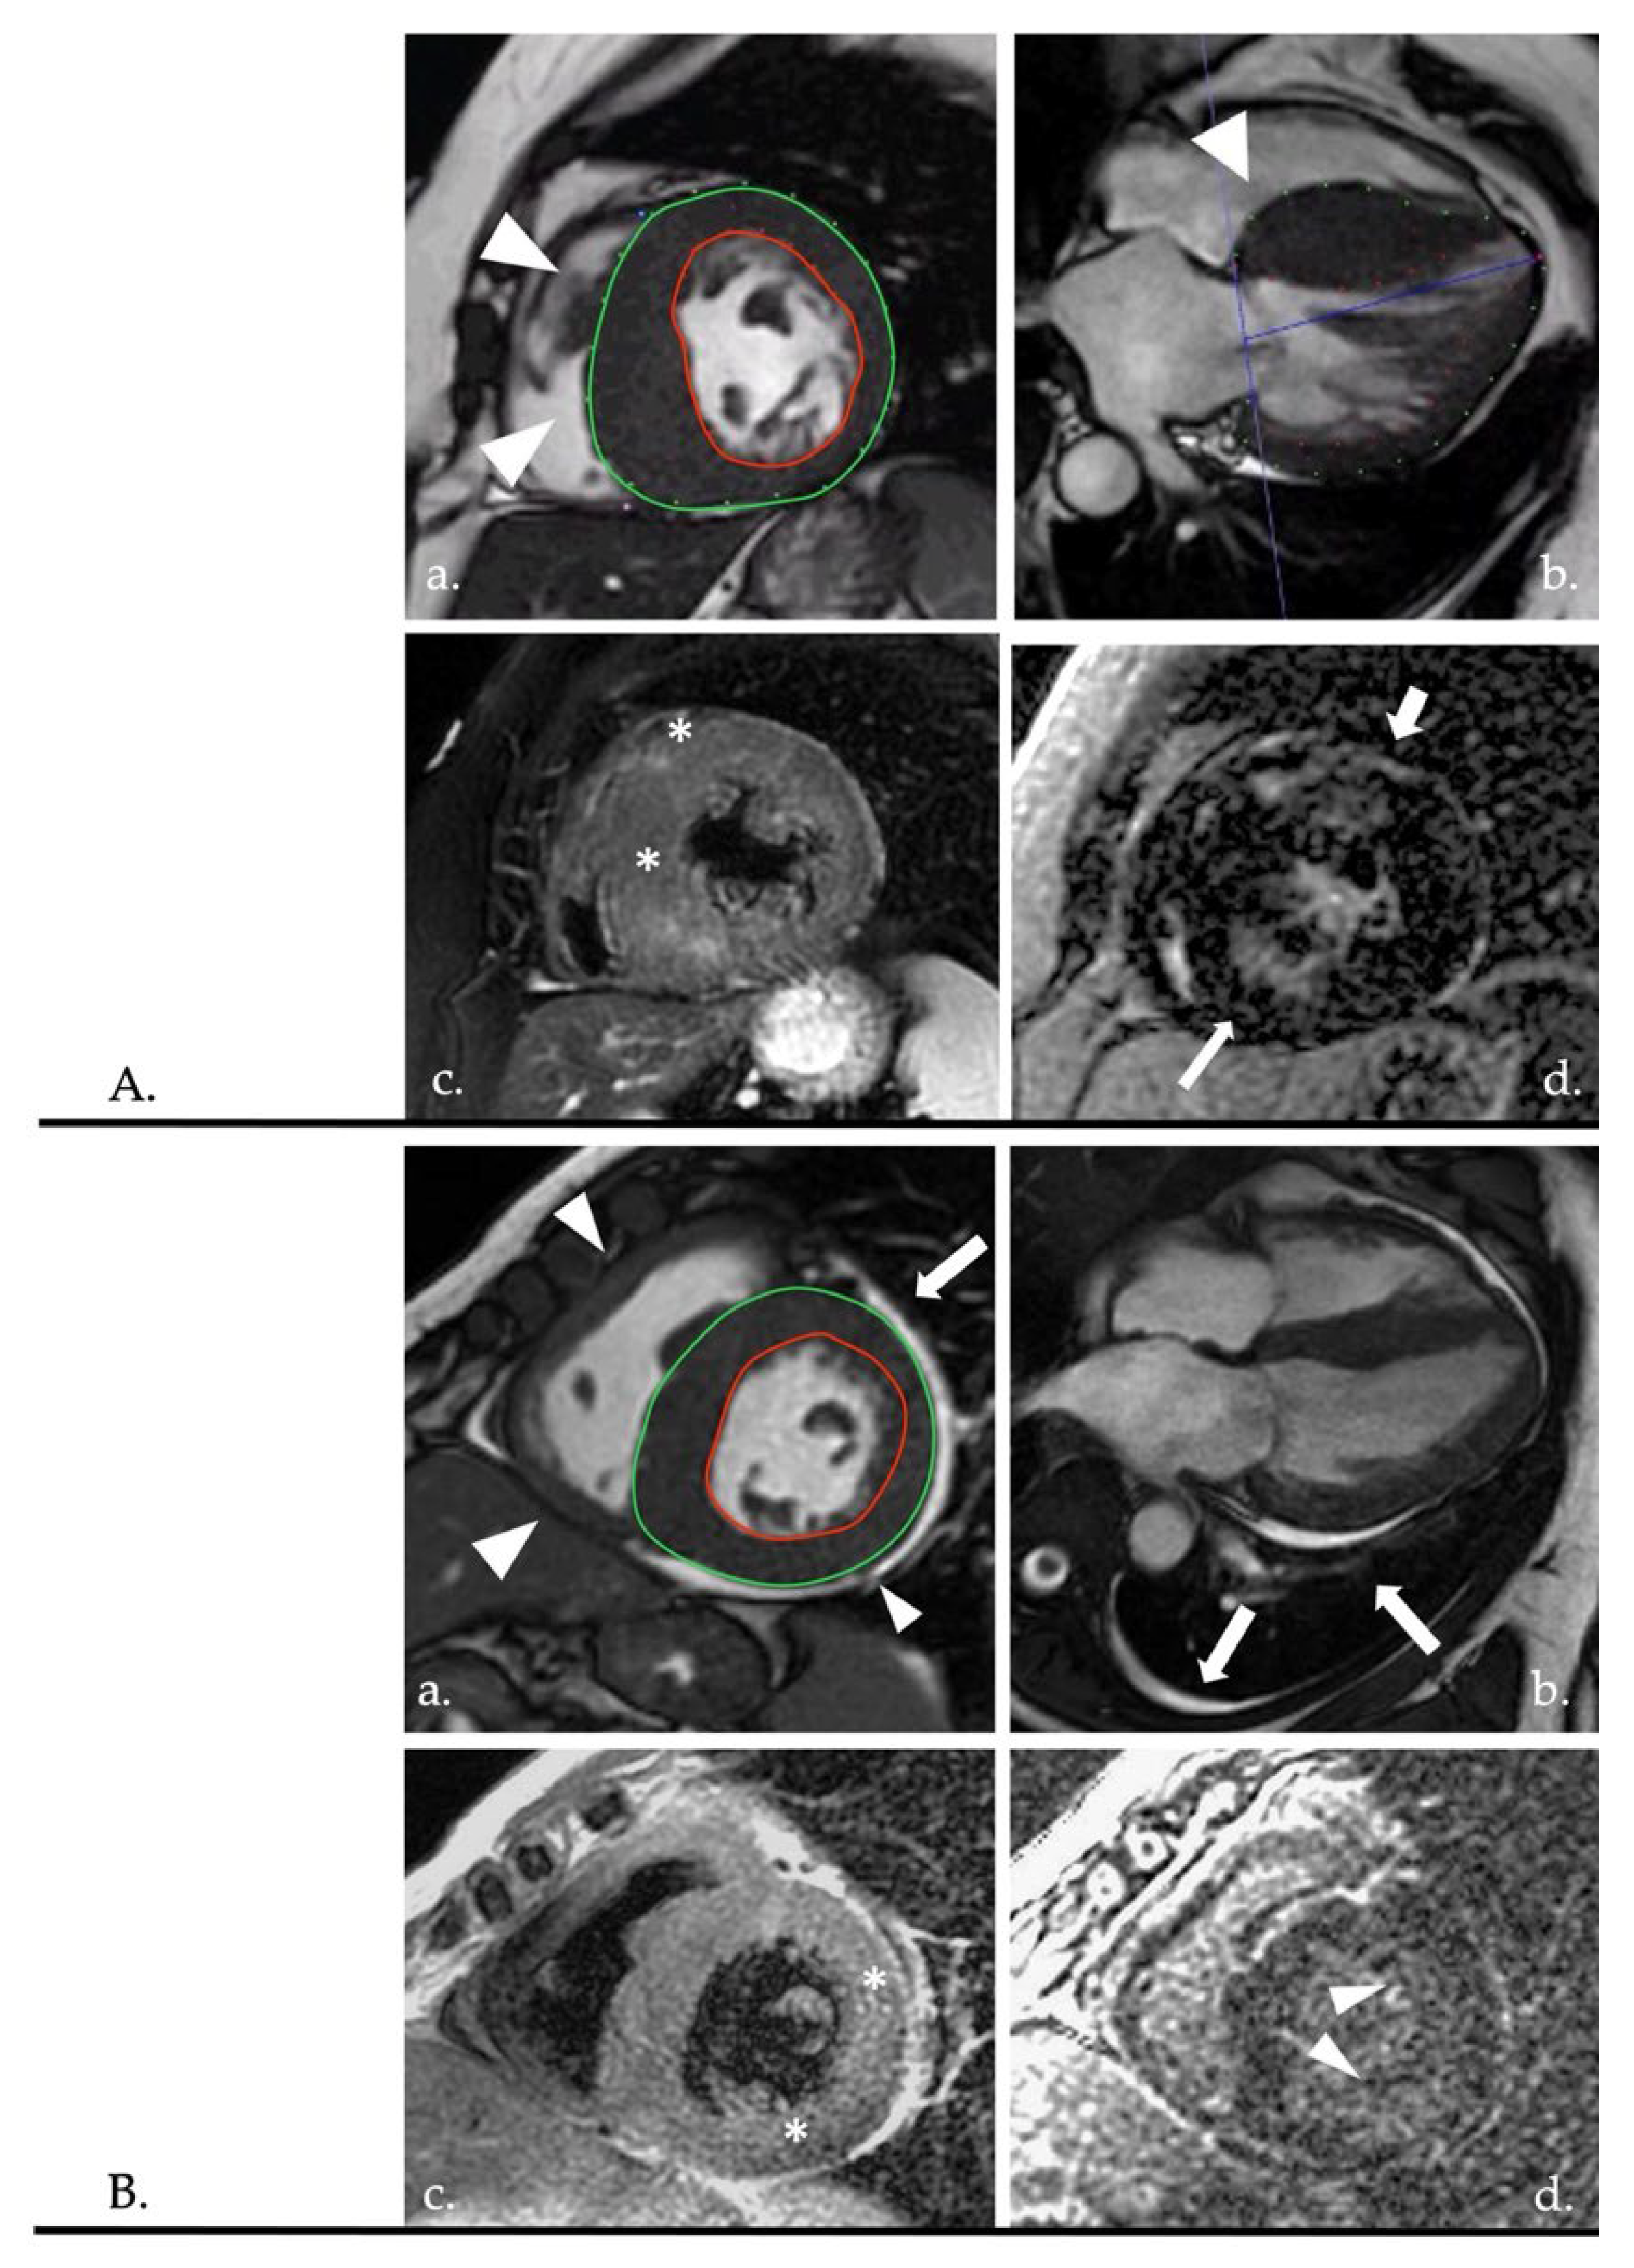

3.2. Dilated Cardiomyopathy (DCM)

Imaging Tips

3.3. Hypertrophic Cardiomyopathy (HCM)

3.4. Restrictive Cardiomyopathy (RCM)